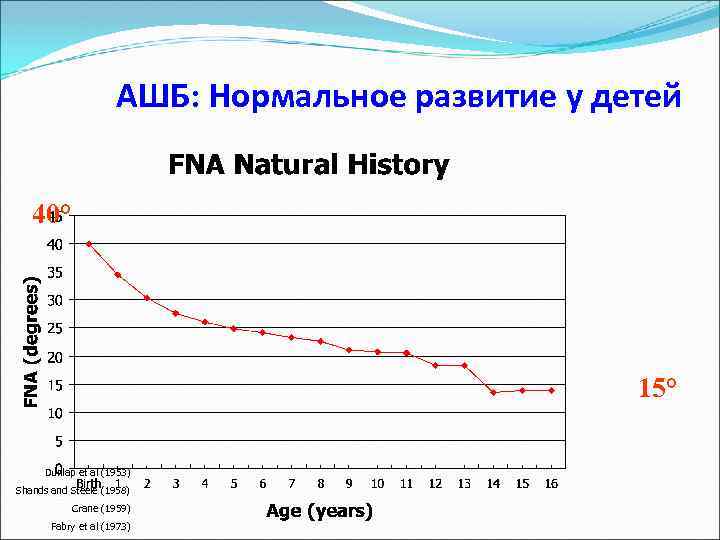

АШБ: Нормальное развитие у детей 40° 15° Dunlap et al (1953) Shands and Steele (1958) Crane (1959) Fabry et al (1973)